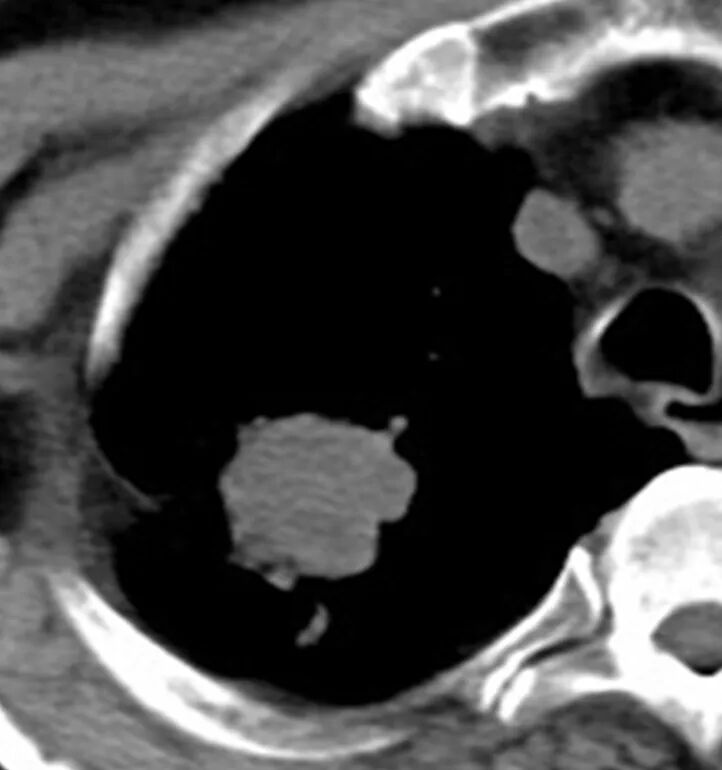

经过王剑飞和肿瘤中心MDT团队的认真讨论,确诊王大伯为右肺恶性肿瘤。“那要手术么?”家属着急地询问着。“大伯80多岁了,心肺功能也不好,手术治疗不耐受的,还是考虑局部治疗,也就是放射治疗”,王剑飞耐心解释着。 经过考虑,大伯和家属都接受了放射治疗的建议。放疗中心副主任刘文君、主治医师阮龙飞为王大伯详细制定了右肺上叶肿块根治性放疗的治疗方案。很快,王大伯便正式开始了治疗。 一年过去了,王大伯早已结束了治疗,而他的定期复查结果令人欣喜——右肺上叶肿块持续缩小,现在已经几乎消失了! “还好听医生话还算及时!”每次看到复查报告,王大伯都十分高兴,一再感谢肿瘤科团队的帮助与悉心照料。 王剑飞提醒市民:发现肿瘤并不是最可怕的,可怕的是不重视或不配合治疗,这是医生最无能为力的局面。 治疗前 治疗结束 治疗结束后2月 治疗结束后10月